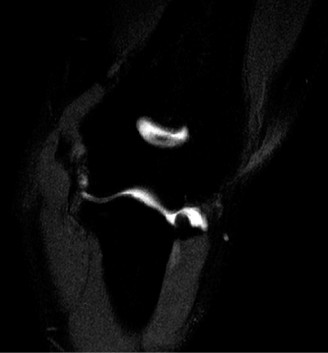

The correct answer is (A). In a young patient, the most likely injury associated with a glenohumeral dislocation is a labral tear (see Fig. 2–31). In an older patient, >40 years old, a rotator cuff tear is more likely. Other possible associated injuries include:

Figure 2–31 MRA demonstrating an anterior labral tear.